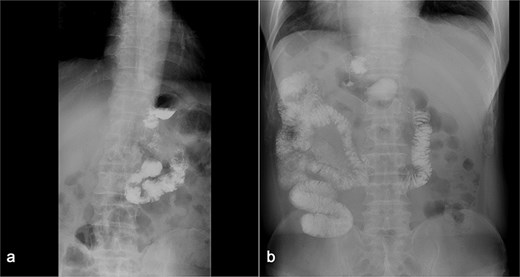

(a) Displays preoperative Gl contrast, while (b) depicts postoperative Gl contrast.